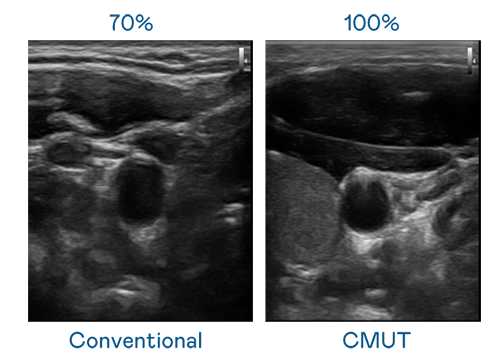

CMUT 技术是一种用电容式微机电元件来产生超音波讯号的技术。与传统 PZT 压电式技术相比,CMUT 频宽增加 30%,更宽频的超音波讯号让影像解析度大幅提升,是实现高影像品质医疗超音波扫描、促进精准医疗发展的关键技术。

大频宽带来超清晰影像

超音波影像的解析度高低,首先取决于探头能发出的讯号频宽。美狮贵宾会 CMUT 可提供高清晰的超音波讯号,提供高频宽、高灵敏度、影像纹理细节更高的超音波影像,协助医护人员缩短影像判读时间及利用精准的医疗影像进行诊断。